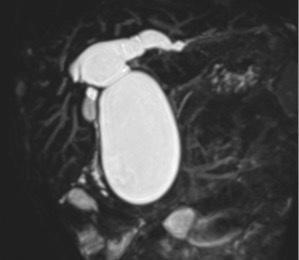

先天性胆道拡張症が疑われる場合は、まずは腹部超音波検査を行います。そこで疑いが強まった場合は、詳しい検査としてMRI検査(Magnetic Resonance cholangiopancreato-graphy:MRCP)を行います。これらの検査でもはっきりと診断できない場合はERCP(endoscopic retrograde cholangiopancreatography:内視鏡的逆行性胆道膵管造影)を行う必要があります。